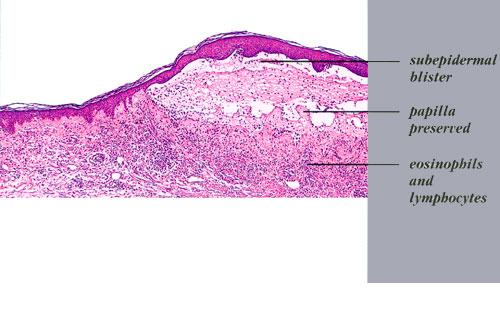

Histopathology.

In early lesions, papillary dermal edema in combination with a cell-poor or cell-rich perivascular lymphocytic and eosinophilic infiltrate is present. The blister arises at the dermal-epidermal junction . In the cell-rich pattern, which correlates clinically with blisters arising on erythematous skin , eosinophilic papillary abscesses may develop with numerous perivascular and interstitial eosinophils intermingled with lymphocytes and neutrophils in the superficial and deep dermis. Early lesions may have the histologic features of eosinophilic cellulitis (Well’s syndrome). Eosinophilic spongiosis may occur. The cell-poor pattem is observed

when blisters develop on relatively normal skin , in which there is usually a scant perivascular lymphocytic infiltrate with few eosinophils, some scattered throughout the dermis and others near the epidermis. The blister contains few inflammatory cells. Epithelial migration and regeneration may result in an intraepidermal split in older blisters. Similar to pemphigus vegetans, a hyperplasia of the epidermis, subepidermal bullae, and accumulations of eosinophils and lymphocytes may be seen.